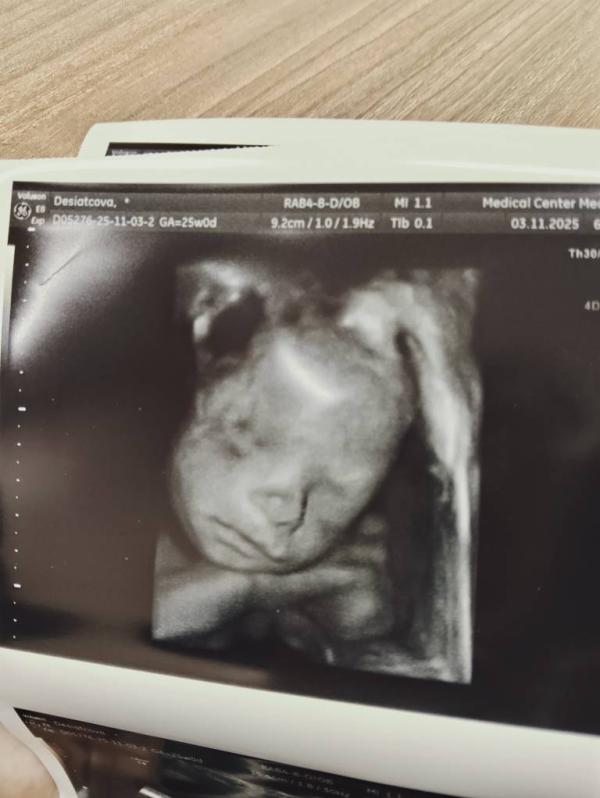

3-4D УЗИ при беременности: как прошло обследование

Ездили сегодня на 3-4D узи, с малышом все хорошо. Развивается по сроку.

Шустрый конечно, не давал себя мерить, и смотреть сердечко, но мы справились 💞💞💞